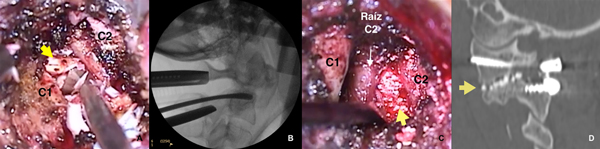

Se procede a realizar disección subperióstica de los remanentes musculares hasta exponer arco posterior y masa lateral de C1, interespacio C1-C2 y pars articularis y masa lateral de C2. Durante la disección del interespacio, se visualiza la raíz saliente de C2, la cual puede ser preservada y retraída hacia superior para exponer la articulación interfacetaria y hacia inferior para que no quede comprimida con el tornillo de C1; o bien, puede ser seccionada.

Luego se procede a la coagulación del plexo venoso adyacente cuyo sangrado debe ser controlado con compresión, coagulación bipolar y/o agentes hemostáticos tipo Surgicel® para poder continuar con el procedimiento.

Con la ayuda de un disector Penfield, se ingresa al espacio interfacetario, se legran los cartílagos articulares ya sea con una cureta o con una mecha diamantada de drill y se coloca sustituto óseo en su interior para lograr una artrodesis anterior (Figura 5).

Figura 5. Artodesis anterior interfacetaria.

A. Imagen intraoperatoria donde se observa el curetaje del cartílago interfacetario. La flecha indica el espacio interfacetario C1-C2. En este caso, la raíz de C2 fue seccionada. B. Imagen de radioscopía intraoperatoria. Disector en el espacio interarticular C1-C2. C. Imagen intraoperatoria: raíz de C2 retraída hacia superior y sustituto óseo en la articulación C1-C2 (flecha amarilla). D. Corte parasagital de TC de columna cervical postoperatoria, donde se observa la artrodesis anterior (flecha).